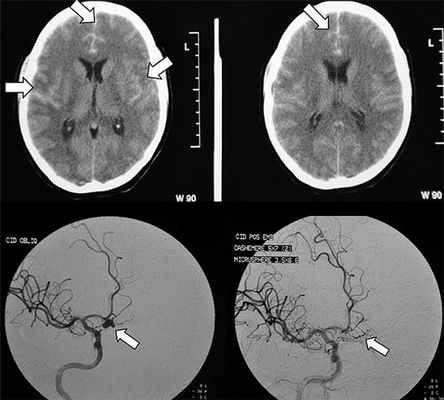

Компьютерная томография

Чувствительность КТ к наличию крови в субарахноидальных пространствах связанна с количеством крови и временем, прошедшим с момента кровоизлияния.

Диагноз подозревается при наличии высокоплотного прокрашивания субарахноидальных пространств.

В большинстве случаев наблюдается около Виллизиевого круга, поскольку большинство мешотчатых аневризм локализуется в этой области (~65%), или в Сильвиевой щели (~30%) ref needed. Небольшие по количеству крови кровоизлияния могут иногда быть выявлены за счет скопления в медножковой цистерне или в виде гиперденсивного треугольника в затылочном роге бокового желудочка [5]. Субарахноидальные кровоизлияния разделяют на 4 категории в соответствии со шкалой Фишера, в зависимости от количества крови.Магнитно-резонансная томография